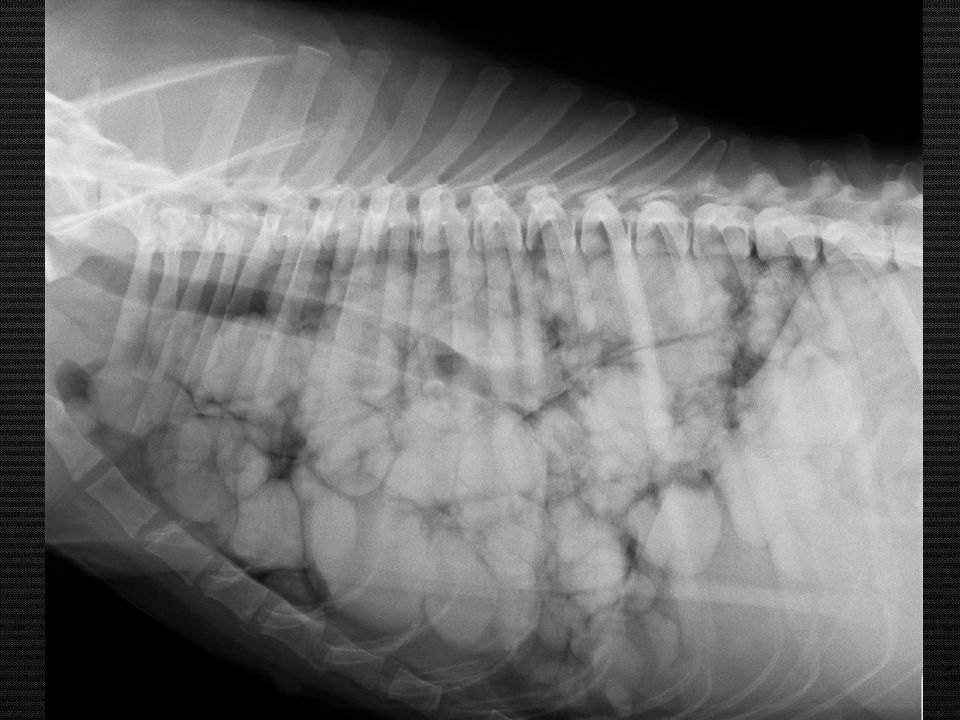

Определите тип затемнений лёгких